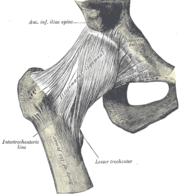

| 26. 11. 2011, 18:10 | Kycelni kloub.png (soubor) |  | 46 kB | Webmaster | (Zdroj: http://commons.wikimedia.org/wiki/File:Gray339.png) | 1 |